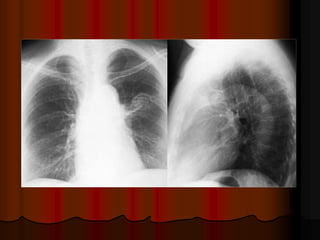

Cavitating squamous cell carcinoma: hang lệch tâm, thành hang dày

Female: cavitary lesions, metastatic squamous cell carcinoma (cervix).